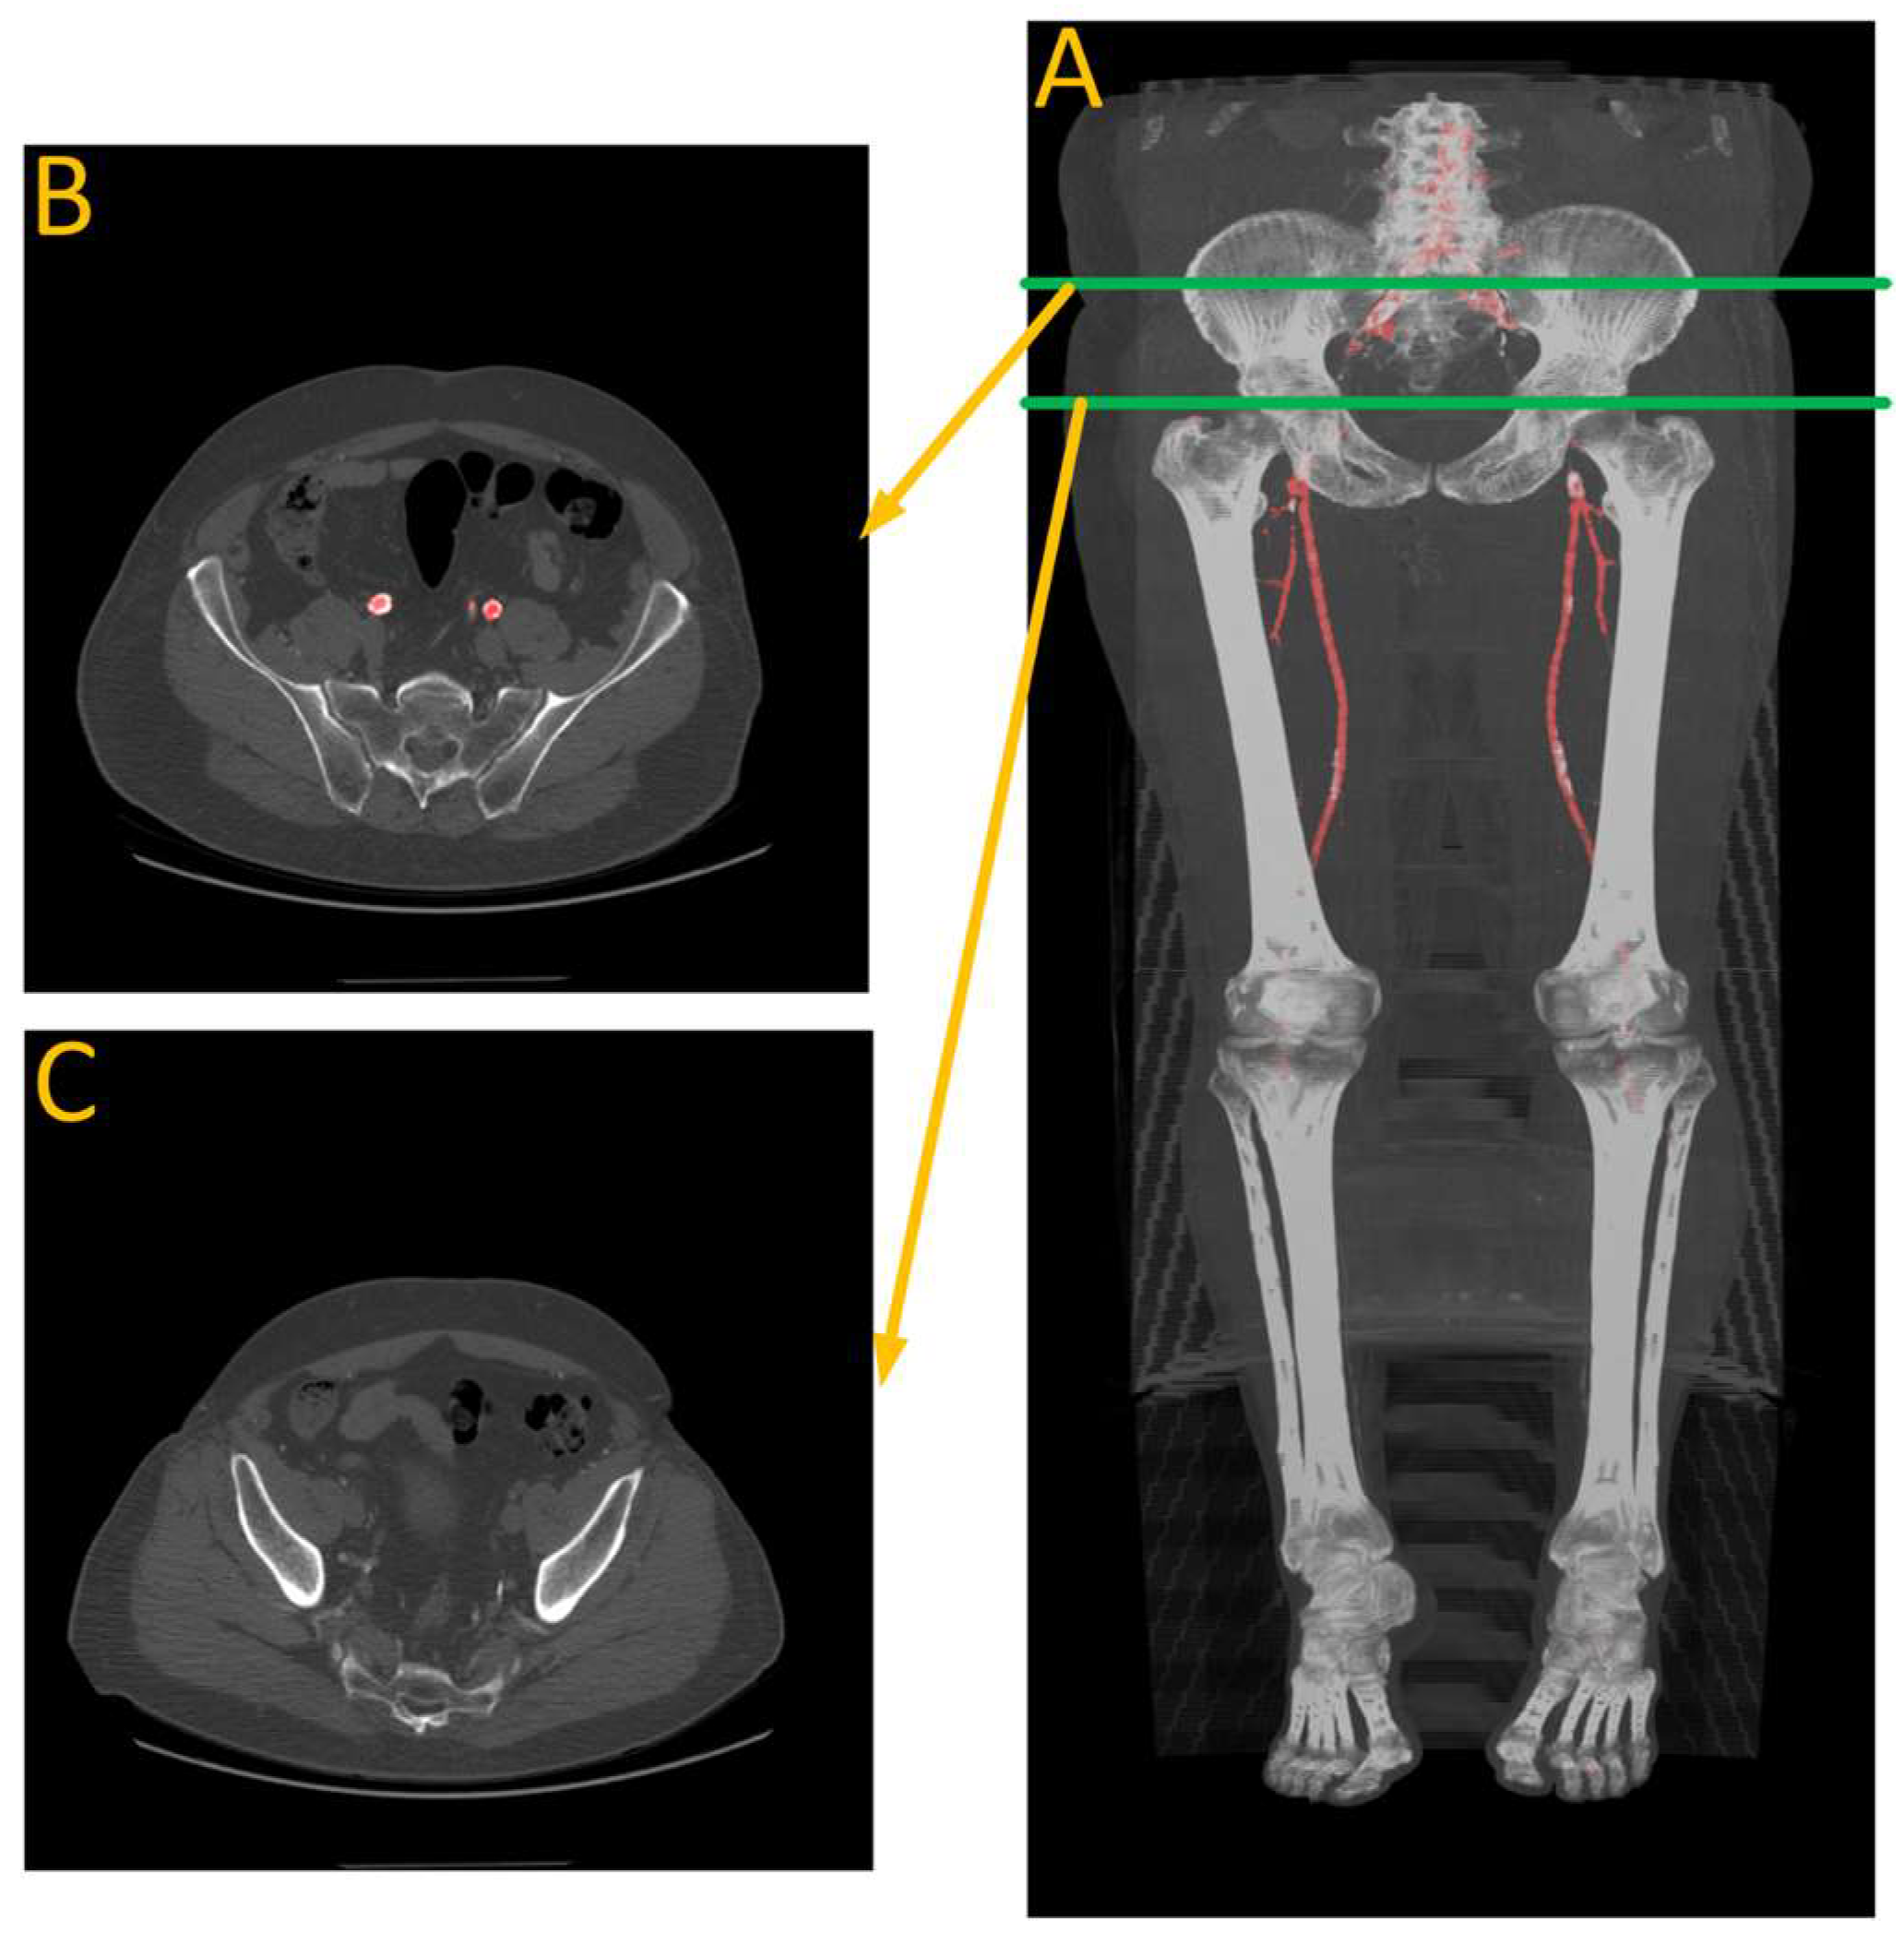

Figure 12.

Performance analysis of the missed segmentation of the proposed model. (A) Displays data from R15, while (B) depicts data from W9. The red regions in the 3D views indicate the model’s predictions of the aorta. In (A), the presence of a screw in the spine distorts the CT images, preventing the model from accurately predicting the aorta in those regions. In (B), the absence of contrast injection in the arteries prior to the CT scan results in the model’s inability to differentiate between arteries and other structures throughout the body. Green line indicate the location of the traverse slice.

Figure 13.

Performance analysis of W22. (A) Is automated artery segmentation. (B) Is the region before the contrast disappears. (C) Is where the model fails to make any predictions due to a lack of contrast in the arteries. Green lines indicate the location of the transverse slices, where red regions represents automated artery segmentation.